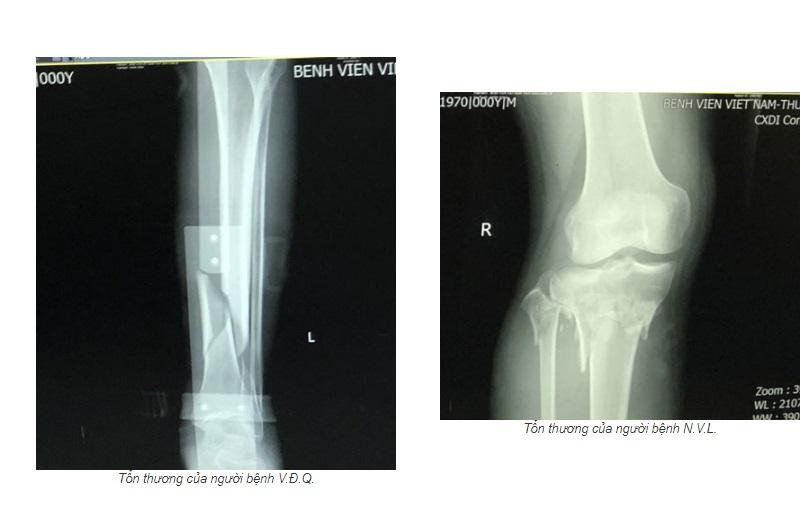

Cả 2 bệnh nhân đều bị tổn thương gãy chân do tai nạn giao thông. Sau khi vào các các cơ sở y tế kiểm tra đều phát hiện gãy xương và được chỉ định nhập viện để điều trị. Tuy nhiên, cả 2 đều xin về để tự điều trị tại nhà bằng cách đắp lá.

Sau khi đắp lá 2 - 3 ngày, các bệnh nhân thấy chân có biểu hiện sưng nề, đau nhiều, chảy dịch mới đến viện để kiểm tra. Trong đó, bệnh nhân N.V.L. (52 tuổi, trú tại Liên vị, Quảng Yên, Quảng Ninh) gãy phức tạp đầu trên 2 xương cẳng chân; bệnh nhân V.Đ.Q. (65 tuổi, trú tại Minh Tân, Thủy Nguyên, Hải Phòng) có tổn thương gãy di lệch 1/3 dưới 2 xương cẳng chân trái.

Theo BSCKII. Hoàng Văn Dũng, với tổn thương của bệnh nhân L., đây là chấn thương phức tạp, có nhiều biến chứng nguy hiểm như hội chứng chèn ép khoang, rối loạn dinh dưỡng Sudeck… Nguy cơ phải cắt bỏ chi cao nếu không được theo dõi và điều trị kịp thời.